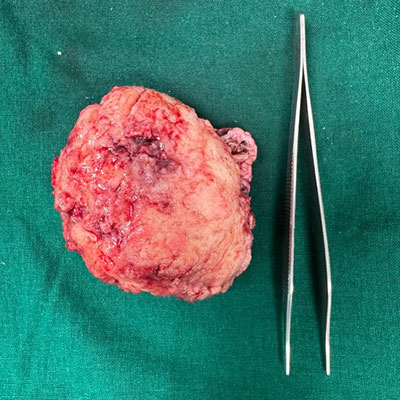

Surgical Highlights